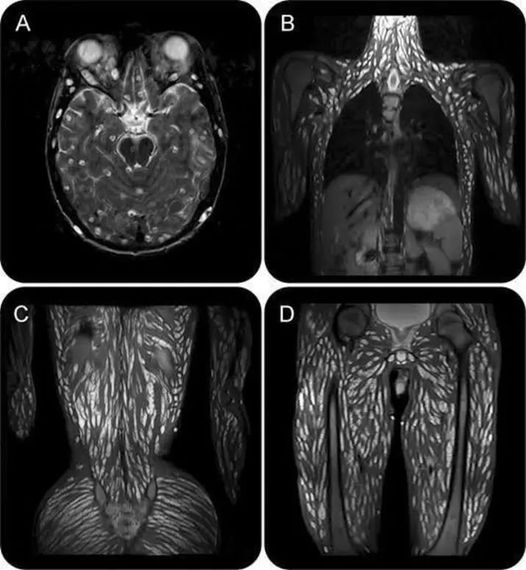

Después de una semana, cuando los parásitos comienzan a reproducirse, las larvas migran fuera del intestino, alcanzando otras zonas del cuerpo a través del torrente sanguíneo. En esta etapa, los síntomas pueden empeorar, especialmente cuando las larvas alcanzan los músculos y se encapsulan en quistes, tal como ocurre en los animales infectados. Los síntomas más comunes en esta fase incluyen:

En infecciones severas, los dolores musculares pueden ser intensos, limitando el movimiento y afectando funciones como la respiración o el habla. Aunque los síntomas pueden durar varios meses, tienden a disminuir una vez que las larvas se encapsulan en los músculos, aunque es posible que algunos efectos, como la fatiga y el dolor residual, persistan durante meses o incluso años.

Aunque la triquinosis no siempre es grave, en casos excepcionales puede haber complicaciones peligrosas. Si una persona ingiere una gran cantidad de larvas, estas pueden afectar órganos importantes del cuerpo. En estos casos, las complicaciones incluyen:

- Inflamación de la pared del corazón (miocarditis)

- Afección del cerebro (encefalitis)

- Inflamación de los pulmones (neumonitis)